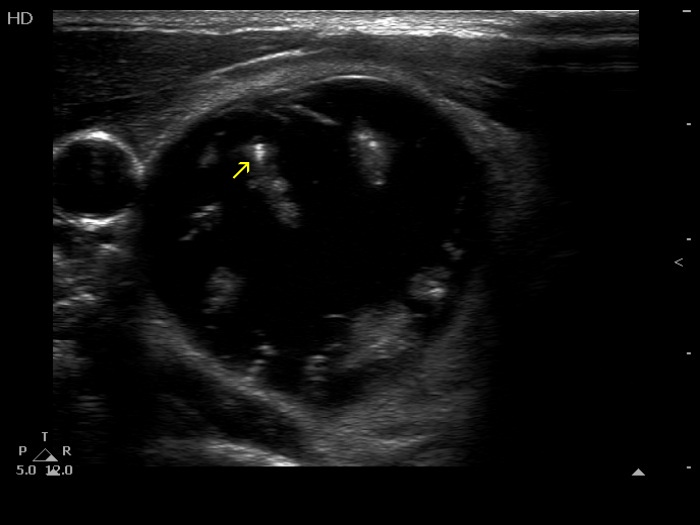

The composition of the nodule - case 1511 (ultrasonographic picture 2b)

Right lobe, another transverse scan. One of the echogenic figures cannot be categorized other than comet tail artifact (yellow arrow).